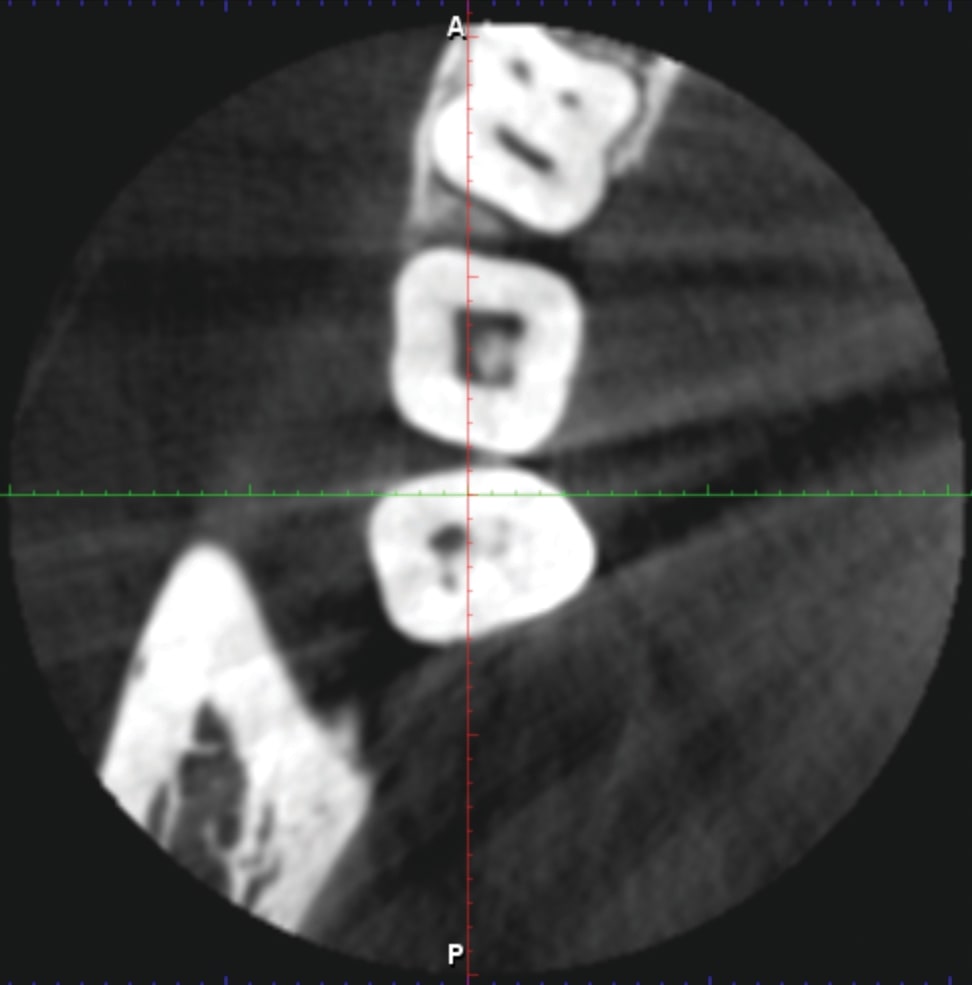

When you are studying the ROI of any dental imaging purchase, note how are artifacts handled within the field of view (FOV), and how that is related to detail. A CBCT machine can run an algorithm artifact removal program to reduce the streaks, but the actual metal object that is causing those streaks must be within the FOV for the artifact removal algorithm to work. The first image shows a small volume 5 X 5 FOV: An artifact removal was run, but streaks and interference are present. The artifact removal algorithm program has no effect on any metal objects that are outside the FOV volume, and your Region of Interest (ROI) can be detail compromised (Figure 1). Therefore, if you are looking for a fracture in a tooth in a small volume size, you need to consider what high-density objects are in the contralateral and surrounding teeth.